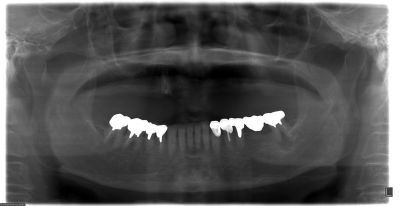

| このように上には、壊れた根が1本あるだけの総入れ歯をされていました。 | |||||||||||||||||||||||||||||||||||

| ハーバード大学では、Dr.Galluciが上下無歯顎の場合、下顎では6本、上顎では8本のインプラントを推奨していました。 ハーバード大学では、ストローマンインプラントを使用しています。 |

| CTを撮って、骨の硬さ(当院のように医科用のCTでないと正確な値が出ません)、骨の幅、上顎洞までの距離などを参考に コンピュータでシミュレーションしながらインプラントの形、サイズ、埋める方向を検討します。 |

| 顎の骨が硬い場合は、円筒状のストローマンインプラントでも良いですが この症例のように日本人の女性の場合は、顎も小さくしかも骨が軟らかいためノーベルのように 円錐状になっていて骨を押し固めながら埋めることができるのが好ましいです。 また、この手術の時は、前日の夜から落ち着く薬を飲んでいただきゆっくりと休まれました。 当日も笑気麻酔をして気持ち良くて、うつらうつらしている間に手術が終わったというのが患者さんの感想でした。 |